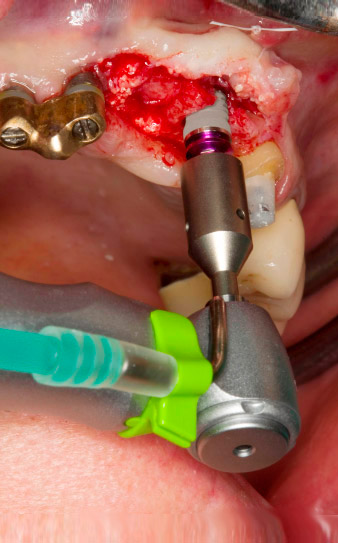

След първичното оздравяване, меките тъкани са оформени посредством базално разположения мост. Два месеца по-късно, обработваното поле е изложено на палатинална алвеоларна инцизия (Фиг 2). Размерите на алвеоларната кост са достатъчни в позиция 22. Фигури 2 и 4 показват препарацията на имплантното ложе, нарязващия винт и имплатирането, използвайки Implantmed.

Новият имплантологичен мотор е използван с подходящите обратни наконечници на W&H.

С цел да се компенсира периодонталната загуба на кост и да се постигне естетически добър резултат, имплантирането е комбинирано с водена костна регенерация (GBR) с ксеногенен заместващ материал и колагенова мембрана (Фиг. 5 и 6).